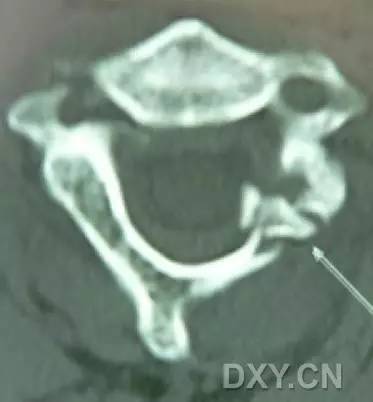

寰椎环的压缩性骨折,骨折是由枢椎压缩性外力引起,骨折多发生在寰椎前侧后侧以及侧方小关节。

第一颈椎双侧性前、后弓骨折,X 线片上很难发现骨折线,有时在正位片上看到 C1 关节突双侧性向外移位,侧位片上看到寰椎前后径增宽及椎前软组织肿胀阴影,CT 检查最为清楚,而 MRI 检查智能显示脊髓损伤情况。

A 图是稳定的 Jefferson 骨折(横韧带完整)轴位像。B 图是不稳定的 Jefferson 骨折(横韧带撕裂)轴位像